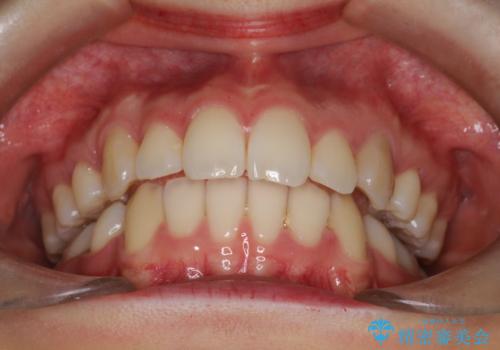

歯並びがコンプレックスで歯を見せて笑うことができなかったとのことですが、歯並びがよくなり、口元を気にせずに笑えるようになったと喜んでいただきました。

目立たない装置をご希望でしたので、上下左右の歯を1本ずつ抜歯してハーフリンガルでの矯正を行いました。